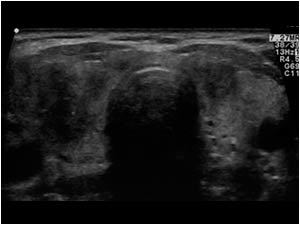

Subacute thyroiditis

AKA :

Low uptake - test of choice

ESR elevated - this is non specific

TFT : elevated FT4/FT3 followed by a hypothyroid 1-3 months after hyperthyroid Phase